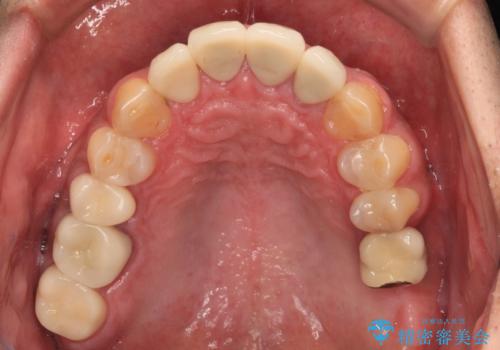

- 黄ばんだ前歯や目立つ奥歯の銀歯をきれいにしたいとのことで来院された患者様です。

しかしながら、左下の抜歯部位は骨欠損が著しく大きく、多大な垂直的骨造成を要するため、3歯を支台としたブリッジによる補綴治療とし、右下のみをインプラント補綴としました。

小さい修復物の銀歯が装着されている歯はセラミックインレーにて、その他はオールセラミッククラウンにて補綴治療を進めることとしました。

矯正治療にも最初は興味を持たれていましたが、抜歯矯正の可能性が高いことや、治療期間、後戻り防止のためのマウスピース使用などが煩わしいと感じ、補綴治療のみを行うこととなりました。